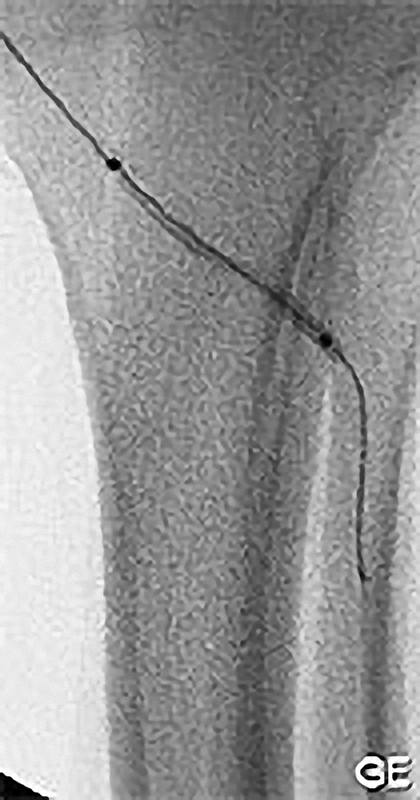

Grundprinzip der Kathetertherapie ist die Gefäßbehandlung über einen millimetergroßen Hautschnitt unter örtlicher Betäubung und das Vorschieben von Plastikschläuchen (Kathetern) in die Gefäße. Über diesen Zugang (meist in der Leisten- oder Ellenbeuge) können Gefäßeinengungen aufgeweitet oder auch Gefäßverschlüsse wiedereröffnet werden (Ballon- oder Stentverfahren). Diese Verfahren werden immer weiter entwickelt und so sind nun auch Behandlungen des Bauchaortenaneurysmatas oder das Einbringen einer Herzklappe auf diesem Wege möglich.

Die PTA (Perkutane Transluminale Angioplastie) im Beckenbereich ist ein minimalinvasives Verfahren zur Behandlung von verengten Beckenarterien. Dabei wird ein dünner Katheter mit einem Ballon über die Leiste in die verengte Arterie eingeführt. Der Ballon wird an der Engstelle entfaltet und dehnt die Arterie auf, um den Blutfluss zu verbessern. Oft wird zusätzlich ein Stent eingesetzt, um die Arterie dauerhaft offen zu halten. Die PTA wird meist in örtlicher Betäubung durchgeführt und ermöglicht eine schnelle Erholung. Sie ist eine bewährte Alternative zur offenen Operation bei Durchblutungsstörungen im Becken- und Beinbereich.